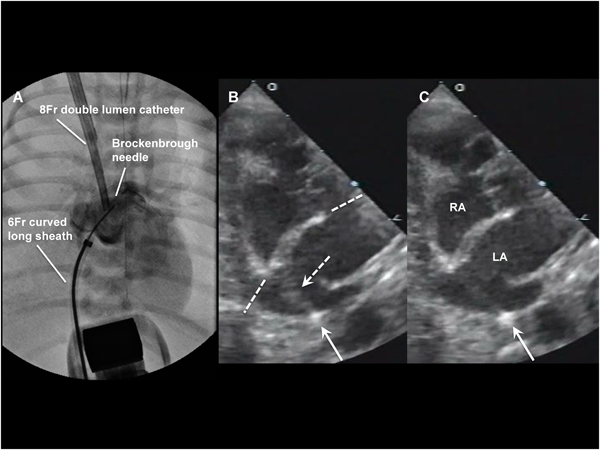

通常のBASが困難,危険,無効な状況としては,肥厚した心房中隔壁,intact atrial septum(IAS),小さいLA,低体重児,両側FVの閉塞・IVC離断などがある.肥厚した心房中隔壁に対して以前はblade atrial septostomyが施行されたが,心房壁や右室流出路(RVOT)の裂傷から死亡する合併症があり,近年はあまり施行されなくなっている2,3).これに対してballoon atrial septal dilationは効果がやや劣るが安全に施行できる.有効な欠損孔を得るためには新生児でも10~12 mm径のバルーンが必要である4,5).inflation/deflationが素早くできるArmada(12 mm×20 mm; Abot)などが適している.当院での経験になるが,Balloon atrial septal dilationにBASを組み合わせることで十分な効果が得られている.IASに対して日本では昨年までBrockenbrough needleを使用せざるを得なかった.新生児・乳児の体格でも心房中隔穿孔は不可能ではないが,特にHLHSでは心房中隔壁が厚く,それを穿孔するだけのLA容積(奥行き)がない場合が多く(Fig. 2),心房壁の穿孔・心タンポナーデの合併率が高くなる6,7).欧米では10数年前からradiofrequency wireを用いた心房中隔穿孔が施行されている(Fig. 3)8).心房中隔に接触させて通電するだけで中隔を穿孔できるので,LAが小さい新生児の肥厚したIASでもより安全に穿孔できる.日本でも2014年8月からNykanen RF wireが使用可能となった(Fig. 4).このwireの直径は0.024″,長さは265 cmで,先端のActive atraumatic tipの直径は0.016″,長さは1.5 mmである.Active tip以外の部分は整形が可能である.Connector cableでGeneratorと接続し,5~10 W,1~10 secの通電で組織の穿通が可能である.現在日本ではPA IVSの肺動脈弁穿孔とIASの心房中隔穿孔に適応があり,その使用には講習が必要である.肥厚した心房中隔のためにBASが無効の場合にはstent septostomyも有効である.留置後抗血小板薬だけでは血栓形成の報告があることから抗凝固療法が必要と思われる9).またstent migrationの報告や強度の内膜増殖を来す期間が不明であり,注意を要する10).

Photograph A shows the left atrial angiogram after transseptal puncture. On transthoracic echocardiogram, immediately before the needle entered the septum, the thick atrial septum (between broken lines) was elongated (broken arrow) and the tip of the needle (arrow) was almost in contact with the left atrial posterior wall (B). Immediately after passing the septum, the tip barely escaped passing through the posterior wall (C; arrow). RA, right atrium; LA, left atrium.